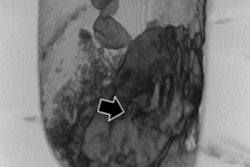

Image shows use of sticks to reassemble the head with the body during mummification."The head of one mummy had completely snapped off, and the embalmer pushed it back on with wooden poles," he said. "We can tell by looking at the neck vertebrae that this had happened postmortem during the drying process. The sticks were part of a running repair."